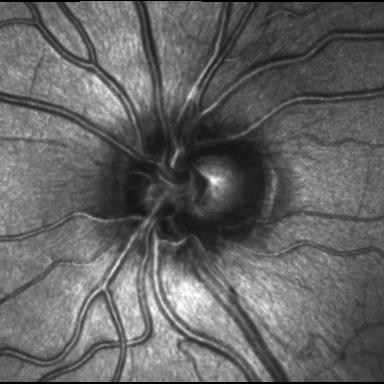

- My ONH (2007)